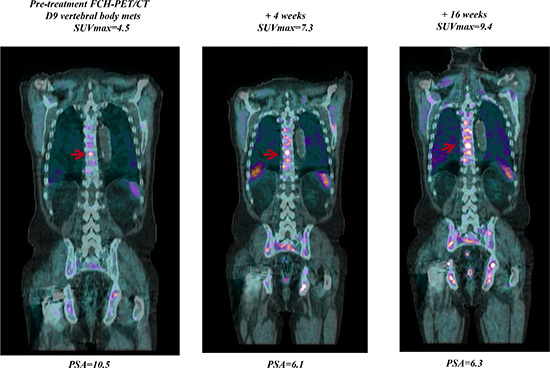

FCH-PET/CT scanning showed 3 CR, 11 PR, 6 SD, and 22 PD, but in 6 of 12 pts with initial PD at FCH-PET/CT a bone flare phenomenon was suspected due to a stable disease at 3-month CT scan associated with a progressive decline of PSA. In one case suspected for bone flare, the PET scan was not repeated due to severe intestinal infection with treatment interruption and following clinical deterioration. In another patient who had a 3-month PSA decline of 60% with SD at 3-month CT scan, the follow-up FCH-PET/CT scanning after 11 weeks confirmed PD with rapidly increasing PSA levels. Thus, overall, bone scan flare, as defined by the combination of PSA decline, initial flare, and subsequent improvement or stability in the following FCH-PET/CT scanning was observed in 4 of 42 (10%) evaluable patients and 4 of 24 (17%) responsive cases. The clinical characteristics of these 4 cases were not significantly different from the study population as a whole, median age was 71 years (range, 57 to 78), median PSA level at baseline was 15.5 ng/mL (range, 1.5–92.2), the maximal decline of PSA was 91%, 73%, 64% and 37%, respectively. The latter case who had a very low baseline PSA level of 1.5 ng/mL and PSA decline to 0.9 ng/mL (37%, lower than the threshold of 50%) was also considered to be of interest and is reported as bone flare. A PSA flare, defined as an initial PSA increment followed by a decline below the PSA baseline level, was reported in one case of bone flare, but also in another patient without bone flare. Of 4 patients with FCH-PET/CT bone flare, 3 had PD after 9, 11 and 13 months, respectively, while one is continuously progression free after 22+ months. A CR was achieved at follow-up FCH-PET/CT in 3 of the 26 (12%) evaluable patients, and was associated with undetectable PSA levels (< 0.03 ng/mL) in 1 case after 5 months on abiraterone. Of 3 patients with nodal disease only, one obtained a CR at first FCH-PET/CT and 2 a PR with a mean SUVmax reduction of 55% and 70%, respectively. Figure 1 to 3 show examples of early FCH-PET/CT effects of abiraterone, including an example of bone flare.

Figure 2: Early FCH-PET-CT progression on abiraterone treatment. Baseline FCH-PET/CT shows multiple areas of increased radiotracer uptake indicative of extensive bone metastases. Treatment with abiraterone resulted in bone progression of FCH-PET/CT scans at week 4 confirmed at week 16.